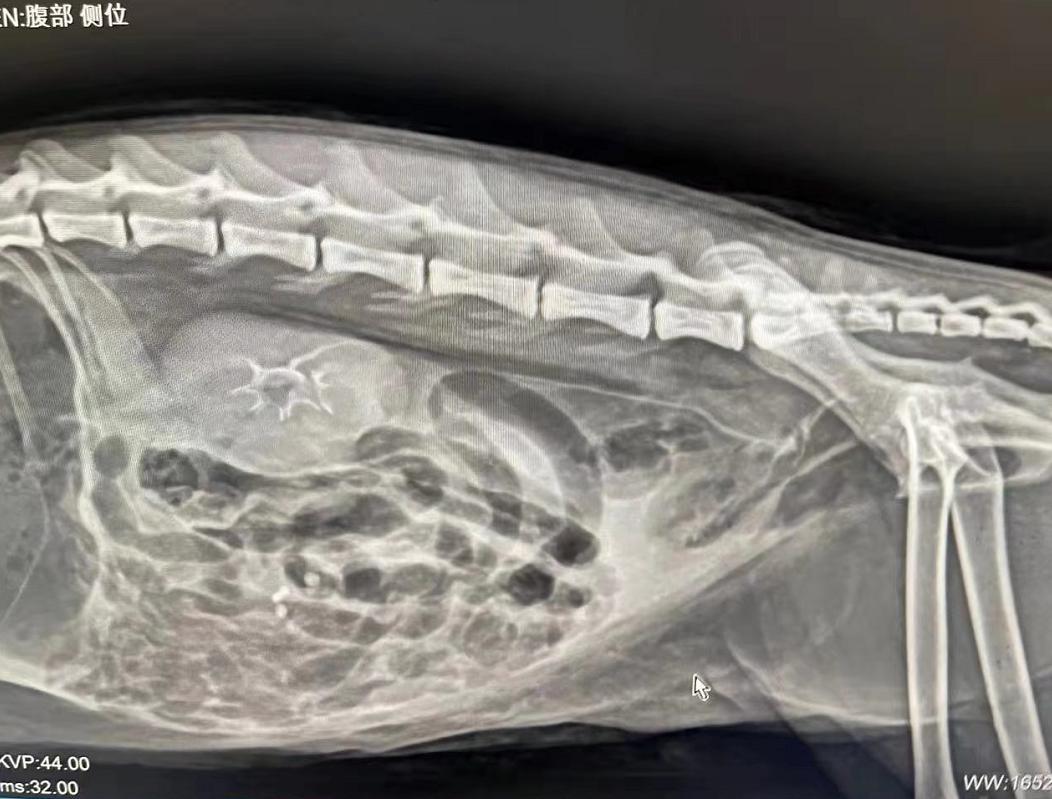

X光检查↓↓

肾脏造影后x光片提示输尿管与膀胱连接处堵塞。